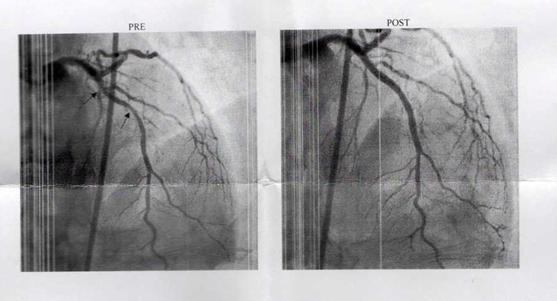

29/11/2018: Spinal Fusion: This week I am having four-level spinal fusion on my lumbar spine (irrevocably damaged by tough hard heavy work from when I was only a child). However, the surgeons have found one disc which is sound so I can have this done, be free of pain and just be a little stiffer getting out of my sleeping bag in the mornings – indeed I might even move to a quilt as the docs are limiting me to 5kg for the next couple of months. That will certainly make me the ultralight hiker! I will find an X-ray of my spine to illustrate this post, but I am in hospital suffering all manner of indignities and cruelties just now so posts are a bit light. Sorry.

I have two of the best spinal surgeons in Australia working on me: Dr Caroline Tan and Dr David Edis. I had the discs removed on Tuesday and replaced with plastic inserts through my side in a procedure known as OLIF. This is apparently the best way to do it. Then on Friday the surgeons will go in though my back to insert the rods and screws which will hold the vertebrae until they fuse. They paint a highly sophisticated artificial chemical construct on the area to create this bone growth and fusion (which will take up to about 3 months).